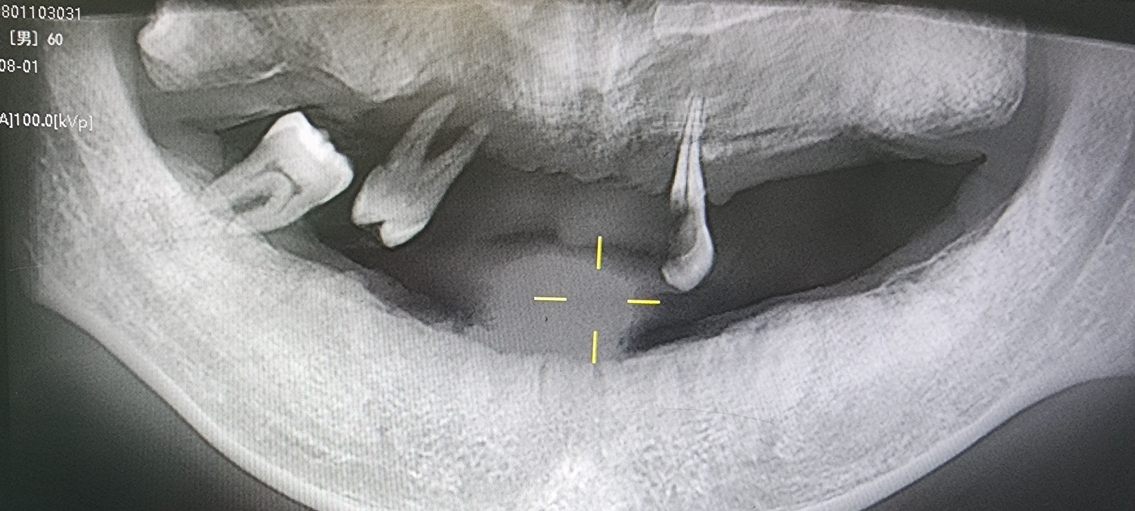

2).Subgingival Calculus (Star of This Article): Found below the gingival margin, within periodontal pockets, and tightly attached to the root surface. Invisible to the naked eye, it can only be detected by dentists using a periodontal probe.

3.Characteristics: Darker in color (dark brown or blackish-green), harder in texture, firmly adhering to tooth roots like cement, and highly destructive to periodontal tissues.